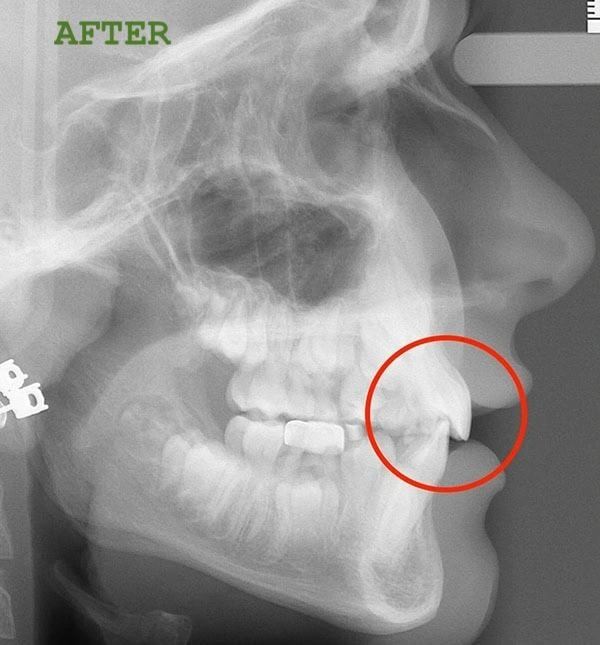

Here’s a common misconception: many parents believe their child’s teeth will improve as they get older. The truth is, if left untreated, conditions like overbites can worsen over time, leading to more severe issues like extractions or even jaw surgery later on. That’s why early treatment—between the ages of 6 and 9—is so important.

Take Kristy, for example. When her daughter, Bailey, came in, we noticed the same overbite problem that headgear would traditionally treat. But instead of resorting to headgear, we tried Invisalign First. The results were nothing short of incredible! Bailey went from hiding her smile to confidently flashing those pearly whites, all without the pain or hassle of headgear.

Kristy initially had some doubts about whether her daughter would lose the aligners or if the treatment would be effective. But after seeing Bailey’s progress, she was amazed. And today, Bailey is smiling more than ever, all thanks to Invisalign First.